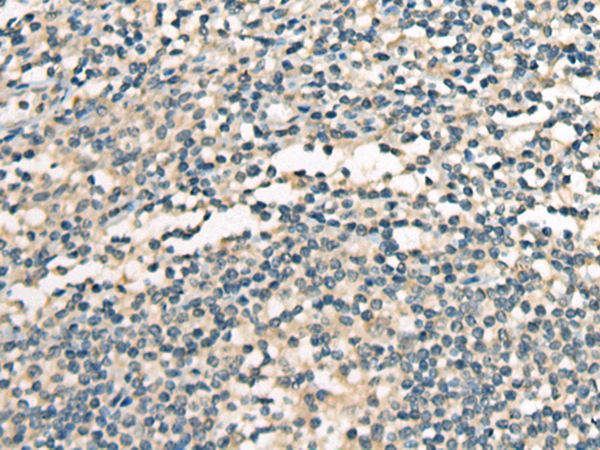

分类: 科研抗体货号: P02461别名: CALC; EFHA3; MPXPS; CBARA1应用: IHC反应种属: Human, Mouse, Rat